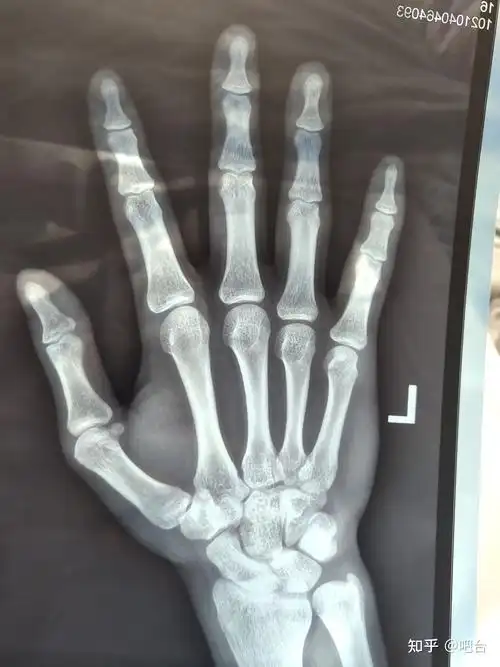

骨骺线接近闭合这么看?

帮忙看下我骨骺线闭合了嘛去年11月拍的好几个月没长了今年16

骨骺线闭合示意图